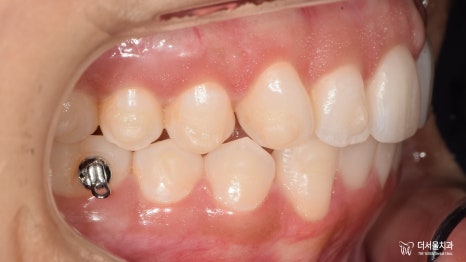

【 초진 】

이분께서는 미국 국적을 갖고 있는 외국인 환자로

첫 번째 치료를 미국에서 진행을 하셨는데요.

음.. 치료를 했던 곳이라는 게 믿을 수 없을 정도로

굉장히 당황스러웠습니다.

마무리가 2급 부정교합으로 되어있더라고요^^..

2급 부정교합 그리고 # 26 크로스 바이트까지

여러 아쉬움이 남는 것으로 확인되었는데요.